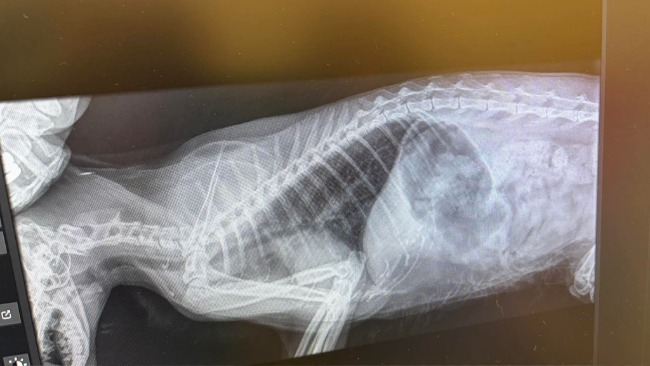

Ma ok 5 lat i już wiemy, że musimy przede wszystkim zadbać o jej przewód pokarmowy. Jelita nie pracują prawidłowo, kotkę męczą wzdęcia i problemy z wypróżnianiem, a jej niepohamowany apetyt i „łapczywość” przy jedzeniu tylko pogarsza sprawę 😞 Kilka wizyt w lecznicy nie przyniosło na tę chwilę rozwiązania problemu. Karmimy Polankę małymi porcjami jedzenia, co pomaga jej się lepiej poczuć, jednak musimy pogłębić diagnostyke by dotrzeć do źródła problemu. Polanka jest ufną, rozmruczaną i przemiłą kotką, a lata tułaczki nie nadszarpnęły tej ufności. Na pewno jednak pogorszyły zdrowie i musimy o to zdrowie zawalczyć 😢